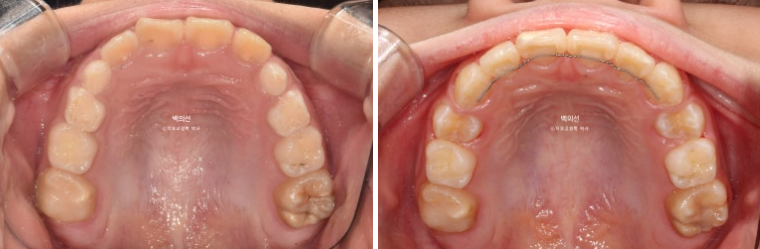

23.12

앞니 중심선이 맞지 않고

엑스레이에서 아래턱의 골격적 비대칭으로 진단이 되었습니다.

이날 공간은 별로 부족하지 않습니다.